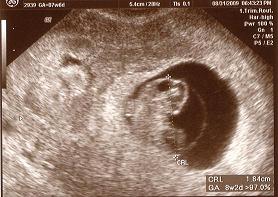

UPDATE:

I am 8 weeks pregnant thanks to one cycle of IVF!

Keep the faith ladies :)

Image Attachment(s):